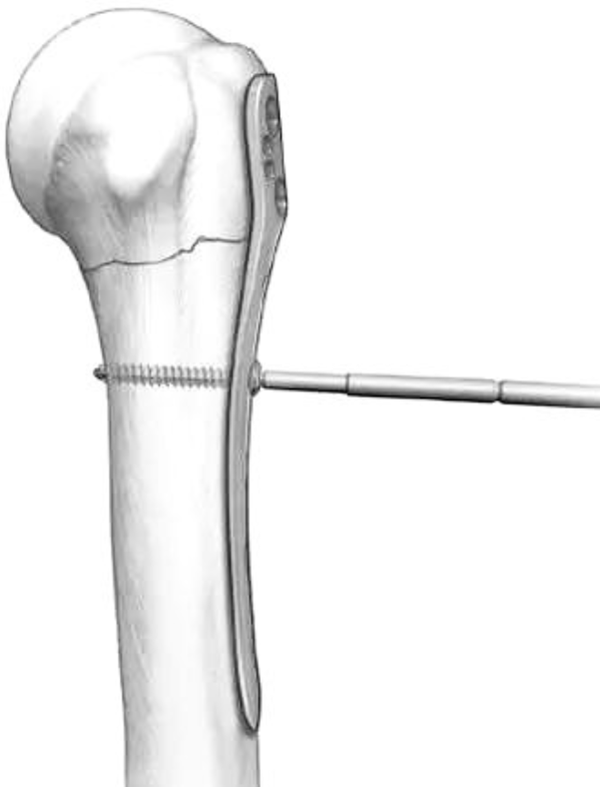

(5)由于胸大肌的牵拉,肱骨干通常都向内移位。

图14 可以先将钢板固定在肱骨头外侧面,而此时骨干可能仍然存在向内移位,在骨折线远端的第一个螺钉孔置入一枚3.5mm皮质骨螺钉将肱骨干向外提拉复位

图15 通过提拉,达到解剖复位